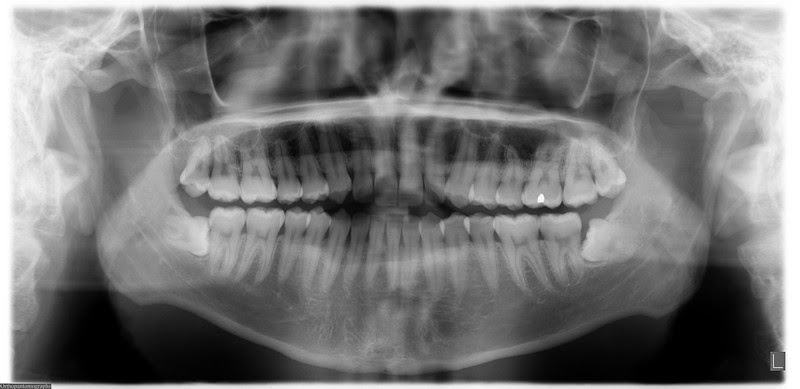

The results showed that compared to the controls, participants with meningioma were more likely to have undergone a type of dental x-ray known as a bitewing exam. This type of exam shows the crowns of the lower and upper teeth at the same time.

The risk of developing meningioma was even higher among participants who reported having a panorex dental x-ray: having this exam yearly or more frequently raised the risk by nearly 3 times, and having it while under the age of 10 by 4.9 times, compared to controls. A panorex exam is one that shows the upper and lower jaws as well as teeth, in the same film.